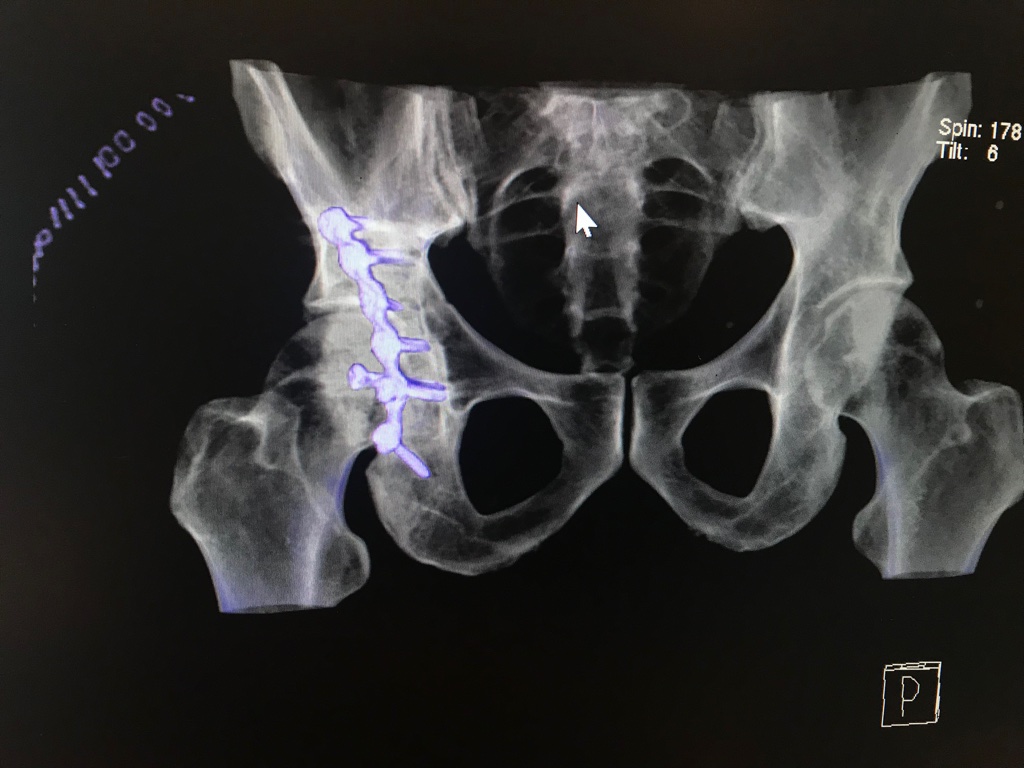

- Una frattura di bacino in un Calatino:

Postoperatorio